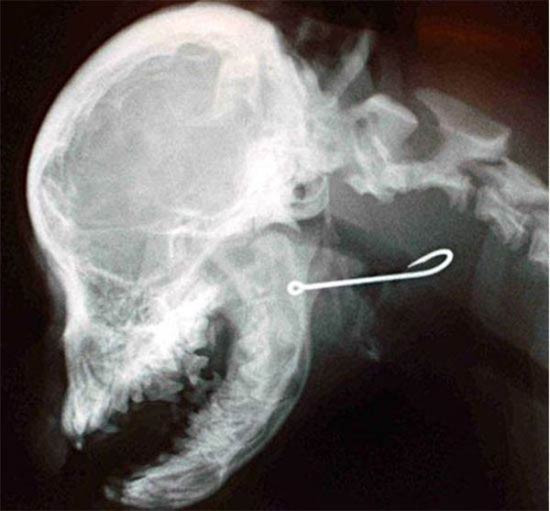

Köpeğin midesinden çıkana bak!